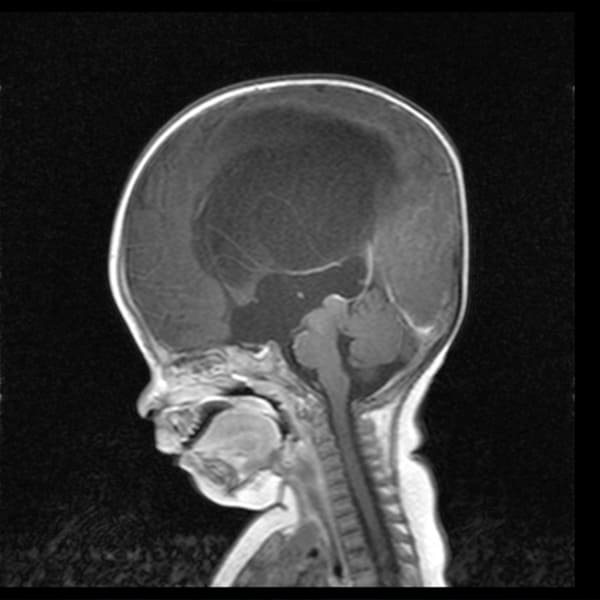

Malformación Chiari

Descompresión de la fosa posterior, se extrae una pequeña sección de hueso de la parte posterior del cráneo, aliviando la presión al darle más espacio al cerebro.